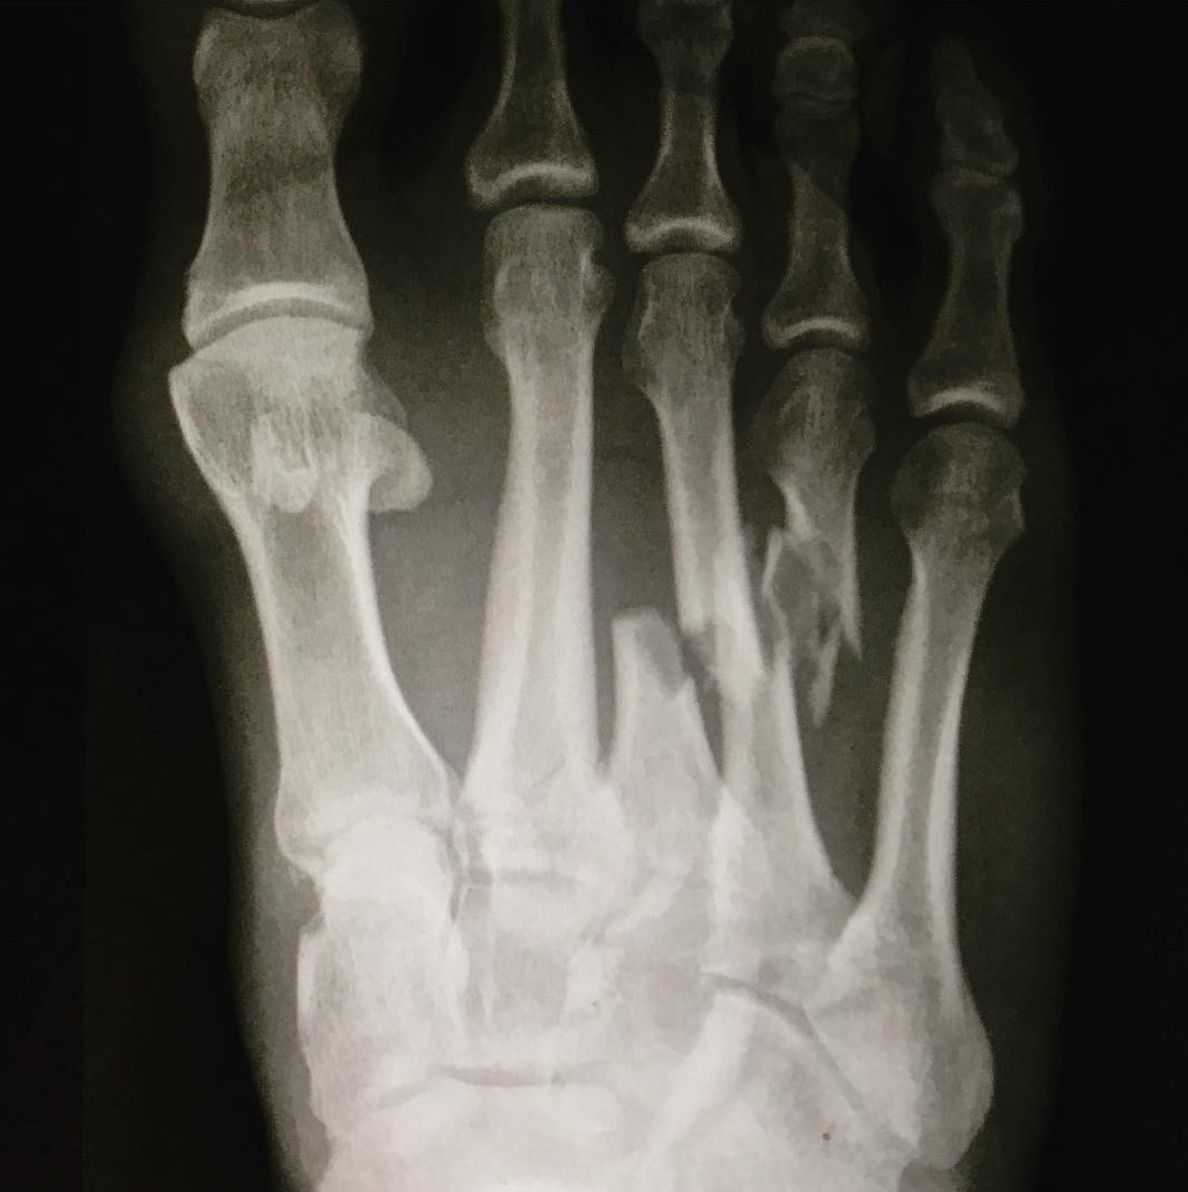

Kelly Slaterが自身のインスタグラムにアップしたレントゲン写真によれば、右足の中指と薬指の中足骨が折れており、手術が必要なうえ、全治6週間を要するだろうとのこと。